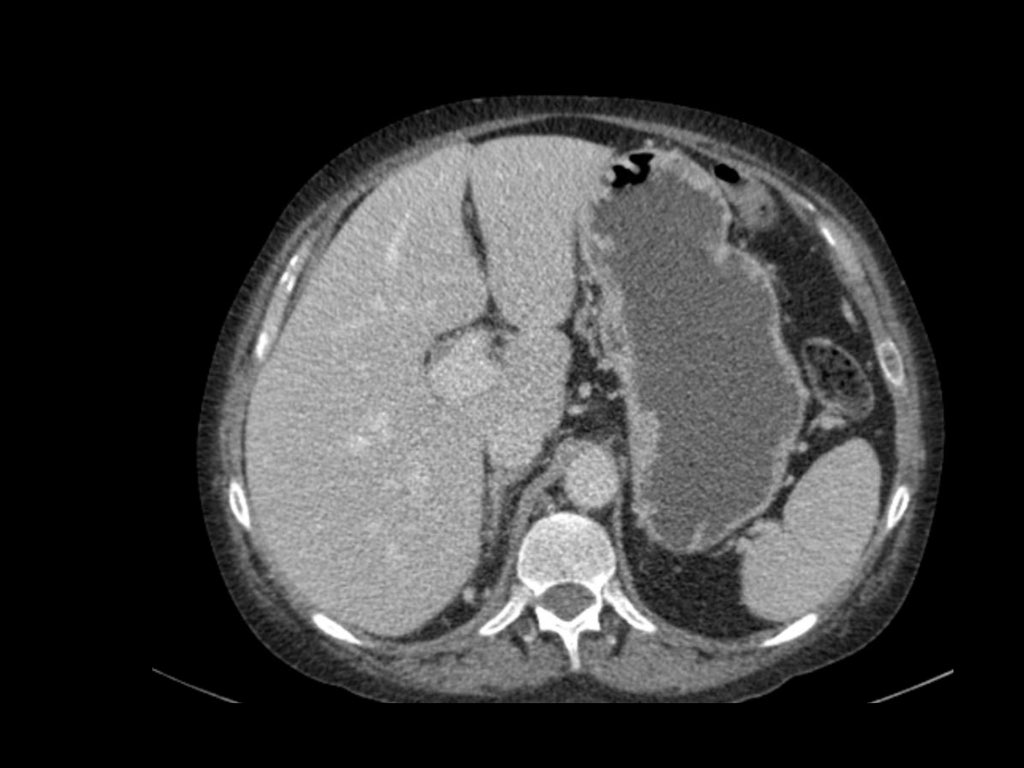

Đặc điểm điển hình của ung thư biểu mô tế bào sáng là ngấm thuốc mạnh trong thì vỏ-tủy (corticomedullary phase).

Điều này có thể khó đánh giá khi tổn thương nhỏ và nằm ở vỏ thận, vốn cũng ngấm thuốc mạnh.

Do đó, thì thận (nephrogenic phase) là thì nhạy cảm nhất để phát hiện các tổn thương này, vì nhu mô thận ngấm thuốc đồng nhất và đậm hơn so với khối u (hình minh họa).

Tổn thương thâm nhiễm ở cực trên thận phải, hầu như không thấy trên ảnh không tiêm thuốc (bên trái), thấy rõ ràng ở thì thận (bên phải). Giải phẫu bệnh xác nhận RCC tế bào sáng

Trong số tất cả các RCC tế bào sáng, khoảng 5% có kiểu tăng trưởng thâm nhiễm.

Mặc dù đây chỉ là một tỷ lệ nhỏ trong số các RCC, nhưng tần suất chung của RCC khiến đây trở thành một chẩn đoán phân biệt quan trọng đối với tổn thương thâm nhiễm dạng hình đậu (bean-type).

RCC thâm nhiễm có tính chất xâm lấn cao và tăng sinh mạch máu.

Tổn thương làm thay đổi cấu trúc nội tại của thận nhưng vẫn bảo tồn đường bờ thận. Các bất thường hệ thống đài bể thận có thể tương tự như những gì thấy trong ung thư biểu mô tế bào chuyển tiếp (transitional cell carcinoma).